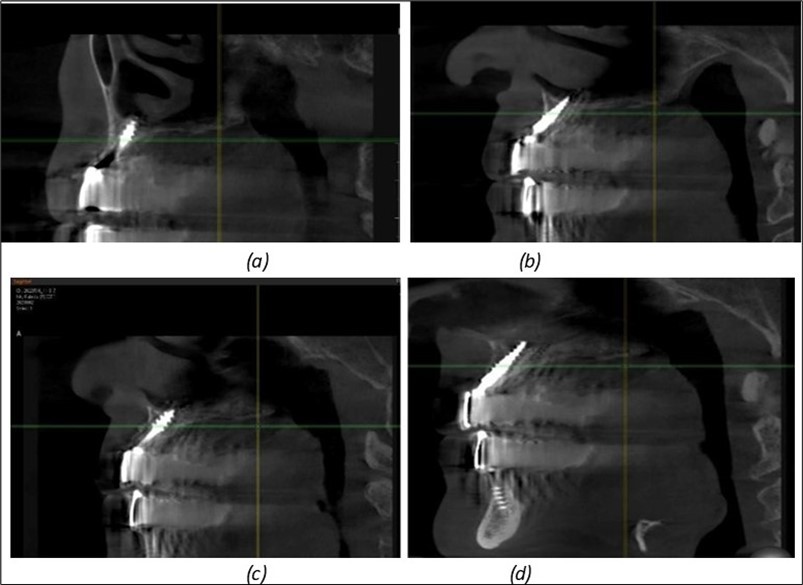

Figure 10.Implants in the palatal sinus cortical area to avoid bone grafting: (a) BCS implant partially fixed in the graft material mass, partially in the palatal cortex; (b) Implant fixed in the palatal cortex at the junction with the nasal cortex, behind the graft material mass.

Figure 11.Implants in the anterior area anchored in the nasal cortex (BCS and TPG): (a), (c) – BCS implants fixed in the nasal cortex; (b), (d) – TPG implants fixed in the second nasal cortex with compression in the trabecular area.

Figure 12.Implants fixed distally in quadrant 4 with fixation at the level of the mylohyoid line: (a) The most distal implant fixed in unaffected bone from the previous restoration; (b) The implant fixed in the area where the two stage implant was removed.

Figure 13.Corticobasal BCS implants fixed between the vestibular and lingual cortices with support on the basal bone: (a) BCS fixed between the lateral cortices; (b) BCS implant with support on the basal cortex.